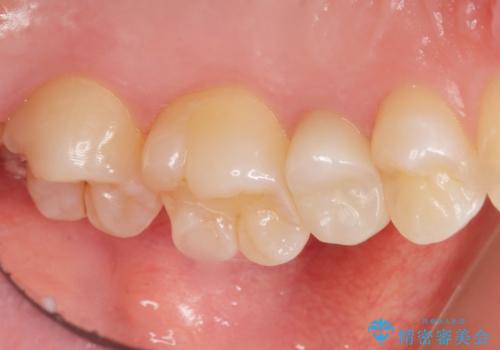

自然な仕上がりにご満足頂けました。

「うわー、自分の歯みたい!すごい!」と喜んで下さいました。

ホワイトニングも行い、口元の印象が明るくなりました。

クラウンの種類:オールセラミッククラウン スタンダード